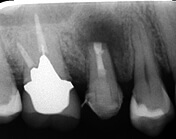

被せ物をした歯の違和感により来院されました

レントゲン写真により経過を確認します

黒い影は骨が溶け膿を持っている

黒い影が無くなり骨の再生が認められ経過は良好です